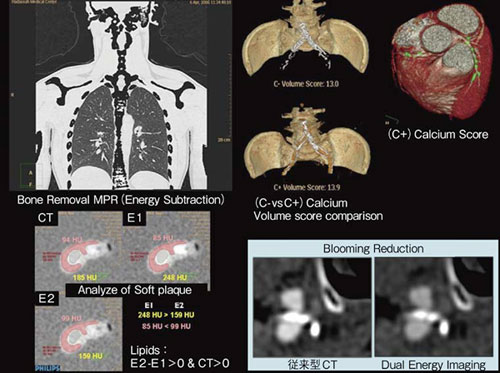

このようなDual Energy Imagingの原理を応用することで,臨床的には大きく2つの利点が期待されている(図1)。

(1) 物質の同定:物質弁別画像を生成することで,カルシウム同定による造影画像からの骨除去(Energy Subtraction)や,腎結石の組成を同定し治療方針を判定することが可能となる。また,心臓領域では,造影画像からのカルシウムスコアリングや,脂質成分の同定によるプラーク評価などがある。

(2) 画質の向上:低エネルギー撮影と高エネルギー撮影の両方の画像を合成することにより,ブルーミングアーチファクトの抑制やビームハードニングの抑制,コントラストの向上がある。

図1 Dual Energy Imagingの特長 |